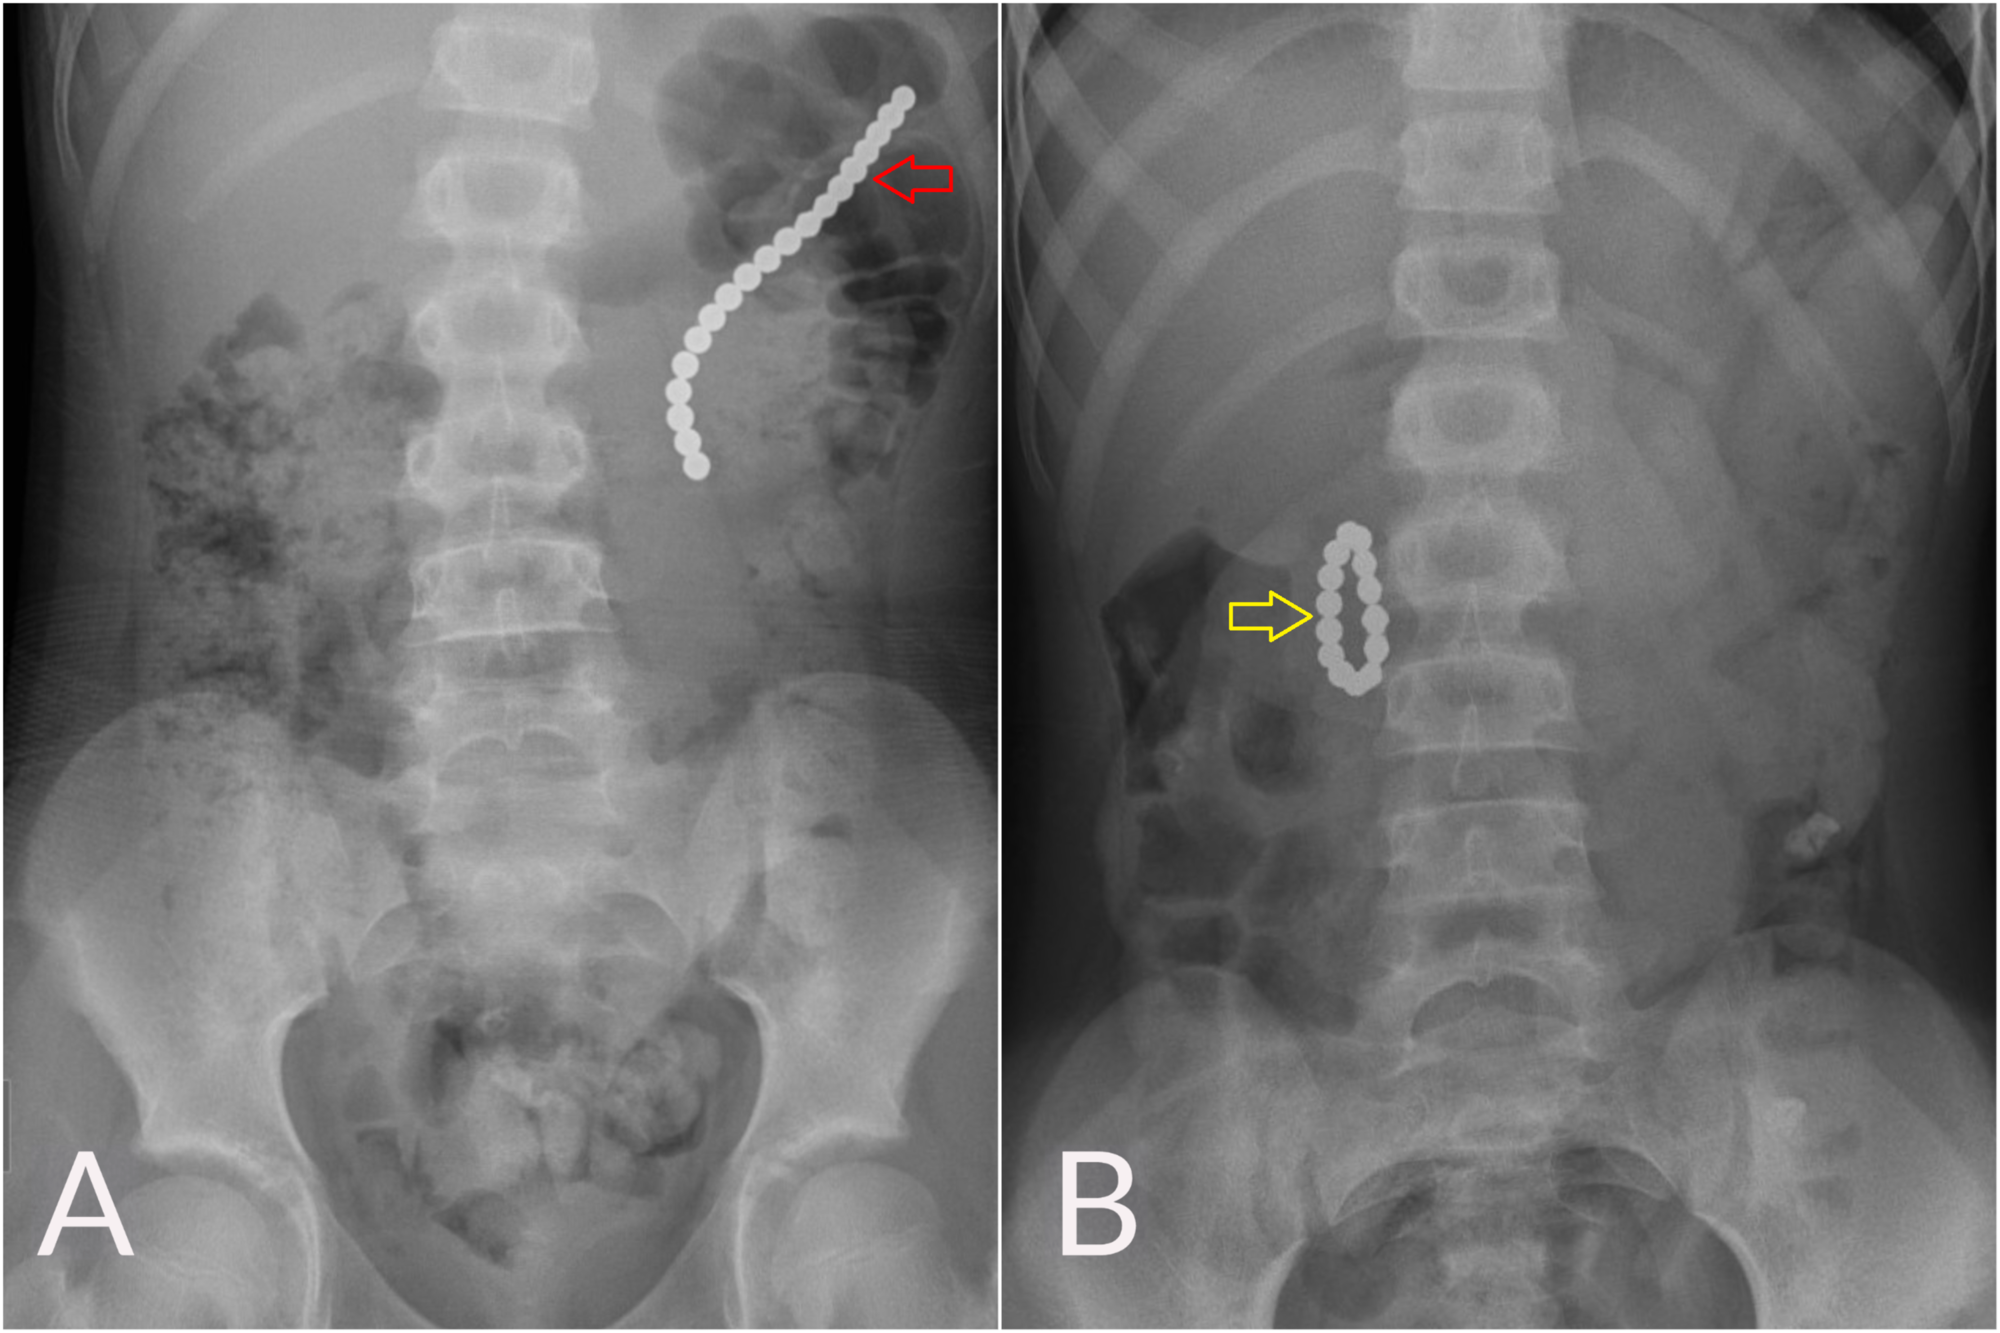

From www.cureus.com

Cureus A Child With a Gastrocolic Fistula After Ingesting An Rings In Stomach It gets its name from richard schatzki, the doctor who discovered it. Learn the symptoms, causes, diagnosis, and treatment of schatzki's ring. A schatzki’s ring is a thin ring of tissue that forms around the lower part of the esophagus above the stomach. The esophagus is the tube that food travels down from your. A schatzki ring is a thin. Rings In Stomach.